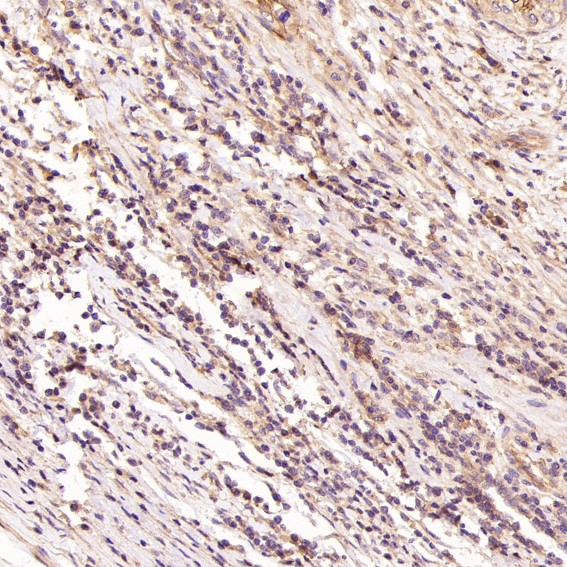

Facts about Cadherin-13.

| Gene Name: | CDH13 |

Highly expressed in heart. In the CNS, expressed in cerebral cortex, medulla, hippocampus, amygdala, thalamus and substantia nigra. No expression detected in cerebellum or spinal cord.